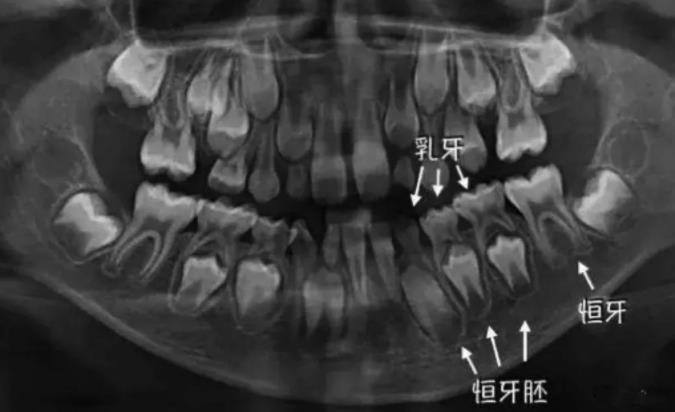

2、新牙沒有萌出,或者說肉眼看不到的這種情況,建議先到醫院去拍個(ge) 牙片,看看下麵是否有恒牙牙胚,以及萌出情況,不建議及時拔除鬆動的乳牙。因為(wei) 乳牙雖然鬆動,但是可能還沒有到脫落的年紀。